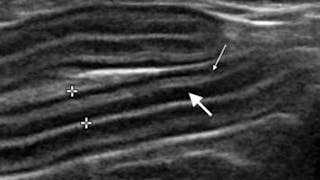

Хронічне захворювання шлунково-кишкового тракту у котів часто є наслідком або запального захворювання кишечника, або кишкової лімфосаркоми, але диференціація між ними може бути проблематичною; Лікарі Аль-Газлат і Еріксон де Резенде діляться кількома корисними для лікаря-клініциста рекомендаціями